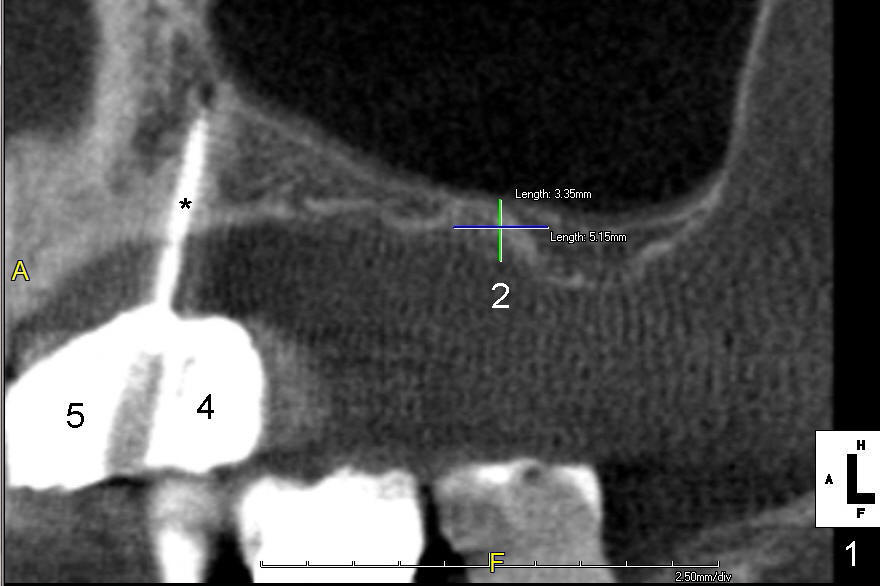

A 56-year-old lady lives out of state. She requests implant treatment for the upper right quadrants. Implants were removed by her previous care provider due to pain and infection. The premolars (Fig.1: #4,5) are provisionalized with a mini-implant (*). CBCT scans (Fig.1,2 (sagittal sections); Fig.3-6 (coronal section) show limited bone height involving the sites of the teeth #2 (Fig.1,3), 3 (Fig.2,4) and 4 (Fig.1,5). The buccolingual width is narrow at the sites of the teeth #4 and 5 (Fig.5,6).